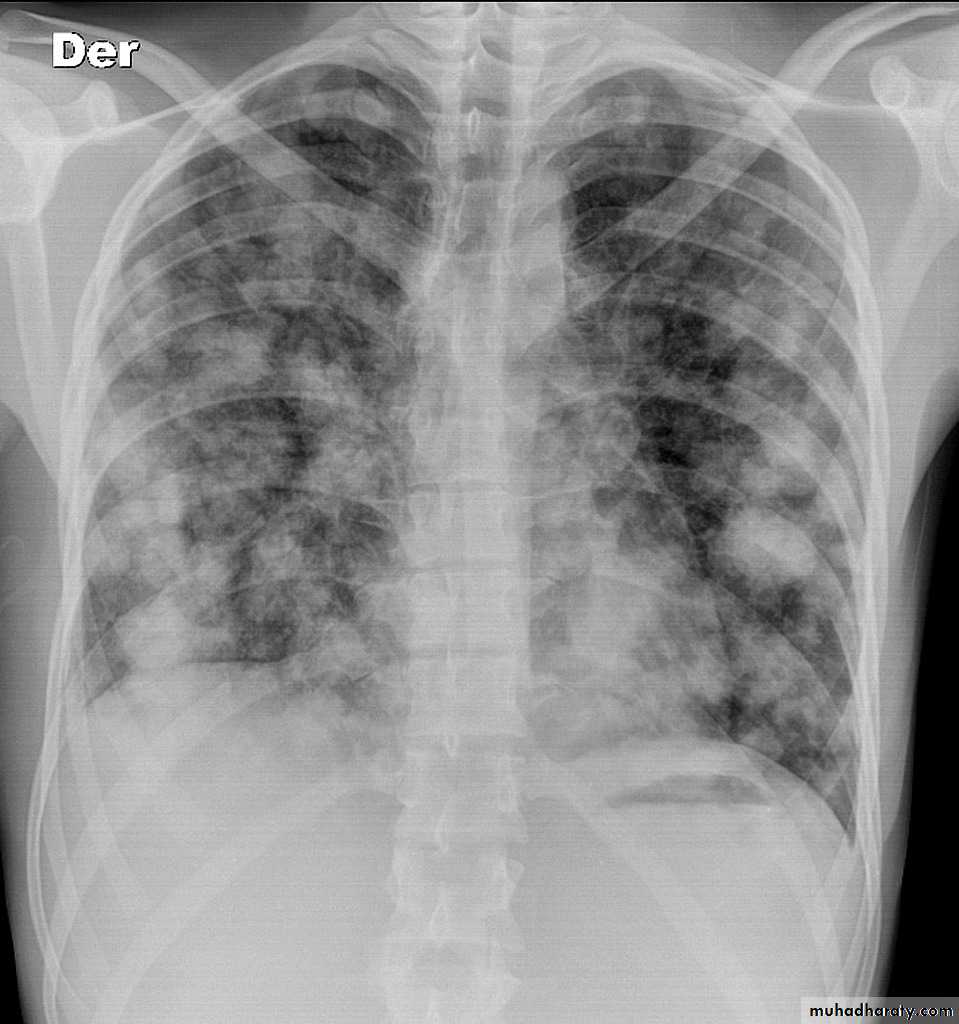

Pulmonary metastases are common and the result of metastatic spread to the lungs from a variety of tumors and can spread via blood or lymphatics.1.Cannonball metastases refer to large well circumscribed, round multiple opacities like cannonballs